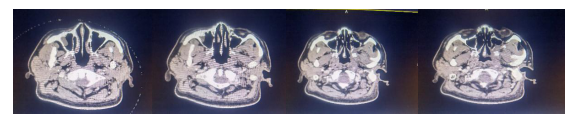

CT检查:鼻咽后壁局部软组织增厚,双侧下颌窝区、右侧耳前皮下软组织内及左侧颈II区多发肿大淋巴结,请与原片对比;双侧上颌窦局部粘膜增厚。双侧腮腺密度不均匀,建议复查。

放疗结束鼻咽CT示:鼻咽左后壁局部软组织增厚,左侧颅底骨受累,同2020-7-27片对照无著变。双侧下颌窝区、双侧腮腺区、右侧耳前皮下组织内及左侧颈II区多发肿大淋巴结,较前缩小;双侧上颌窦粘膜增厚,同前无著变。